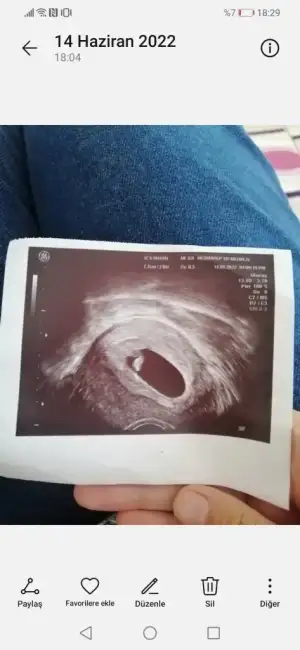

Evt cnm karından bakildiYa yok ben çok anlamıyorum bu ana sagdaysa erkek soldaysa kız kese yuvarlaksa kız fasulye gibiyse erkek diyorlar hep genelde de tutuyorbu ultrason karından mı bakıldı

Erkek sanki benim oğlumun kesesine benziyir biraz bidr benimkide böyle sağ taraftaydiEvt cnm karından bakildi

Merhaba ilk keseyi atsam tahminde bulunur musunuz :) 5 haftalikKaç haftalık burda ilk kese resmi varmı daha küçük olan

Başka varmı daha belli olan sanki benim oğlumun kesesine benziyor biraz ama içimden de kız geçtiMerhaba ilk keseyi atsam tahminde bulunur musunuz :) 5 haftalik